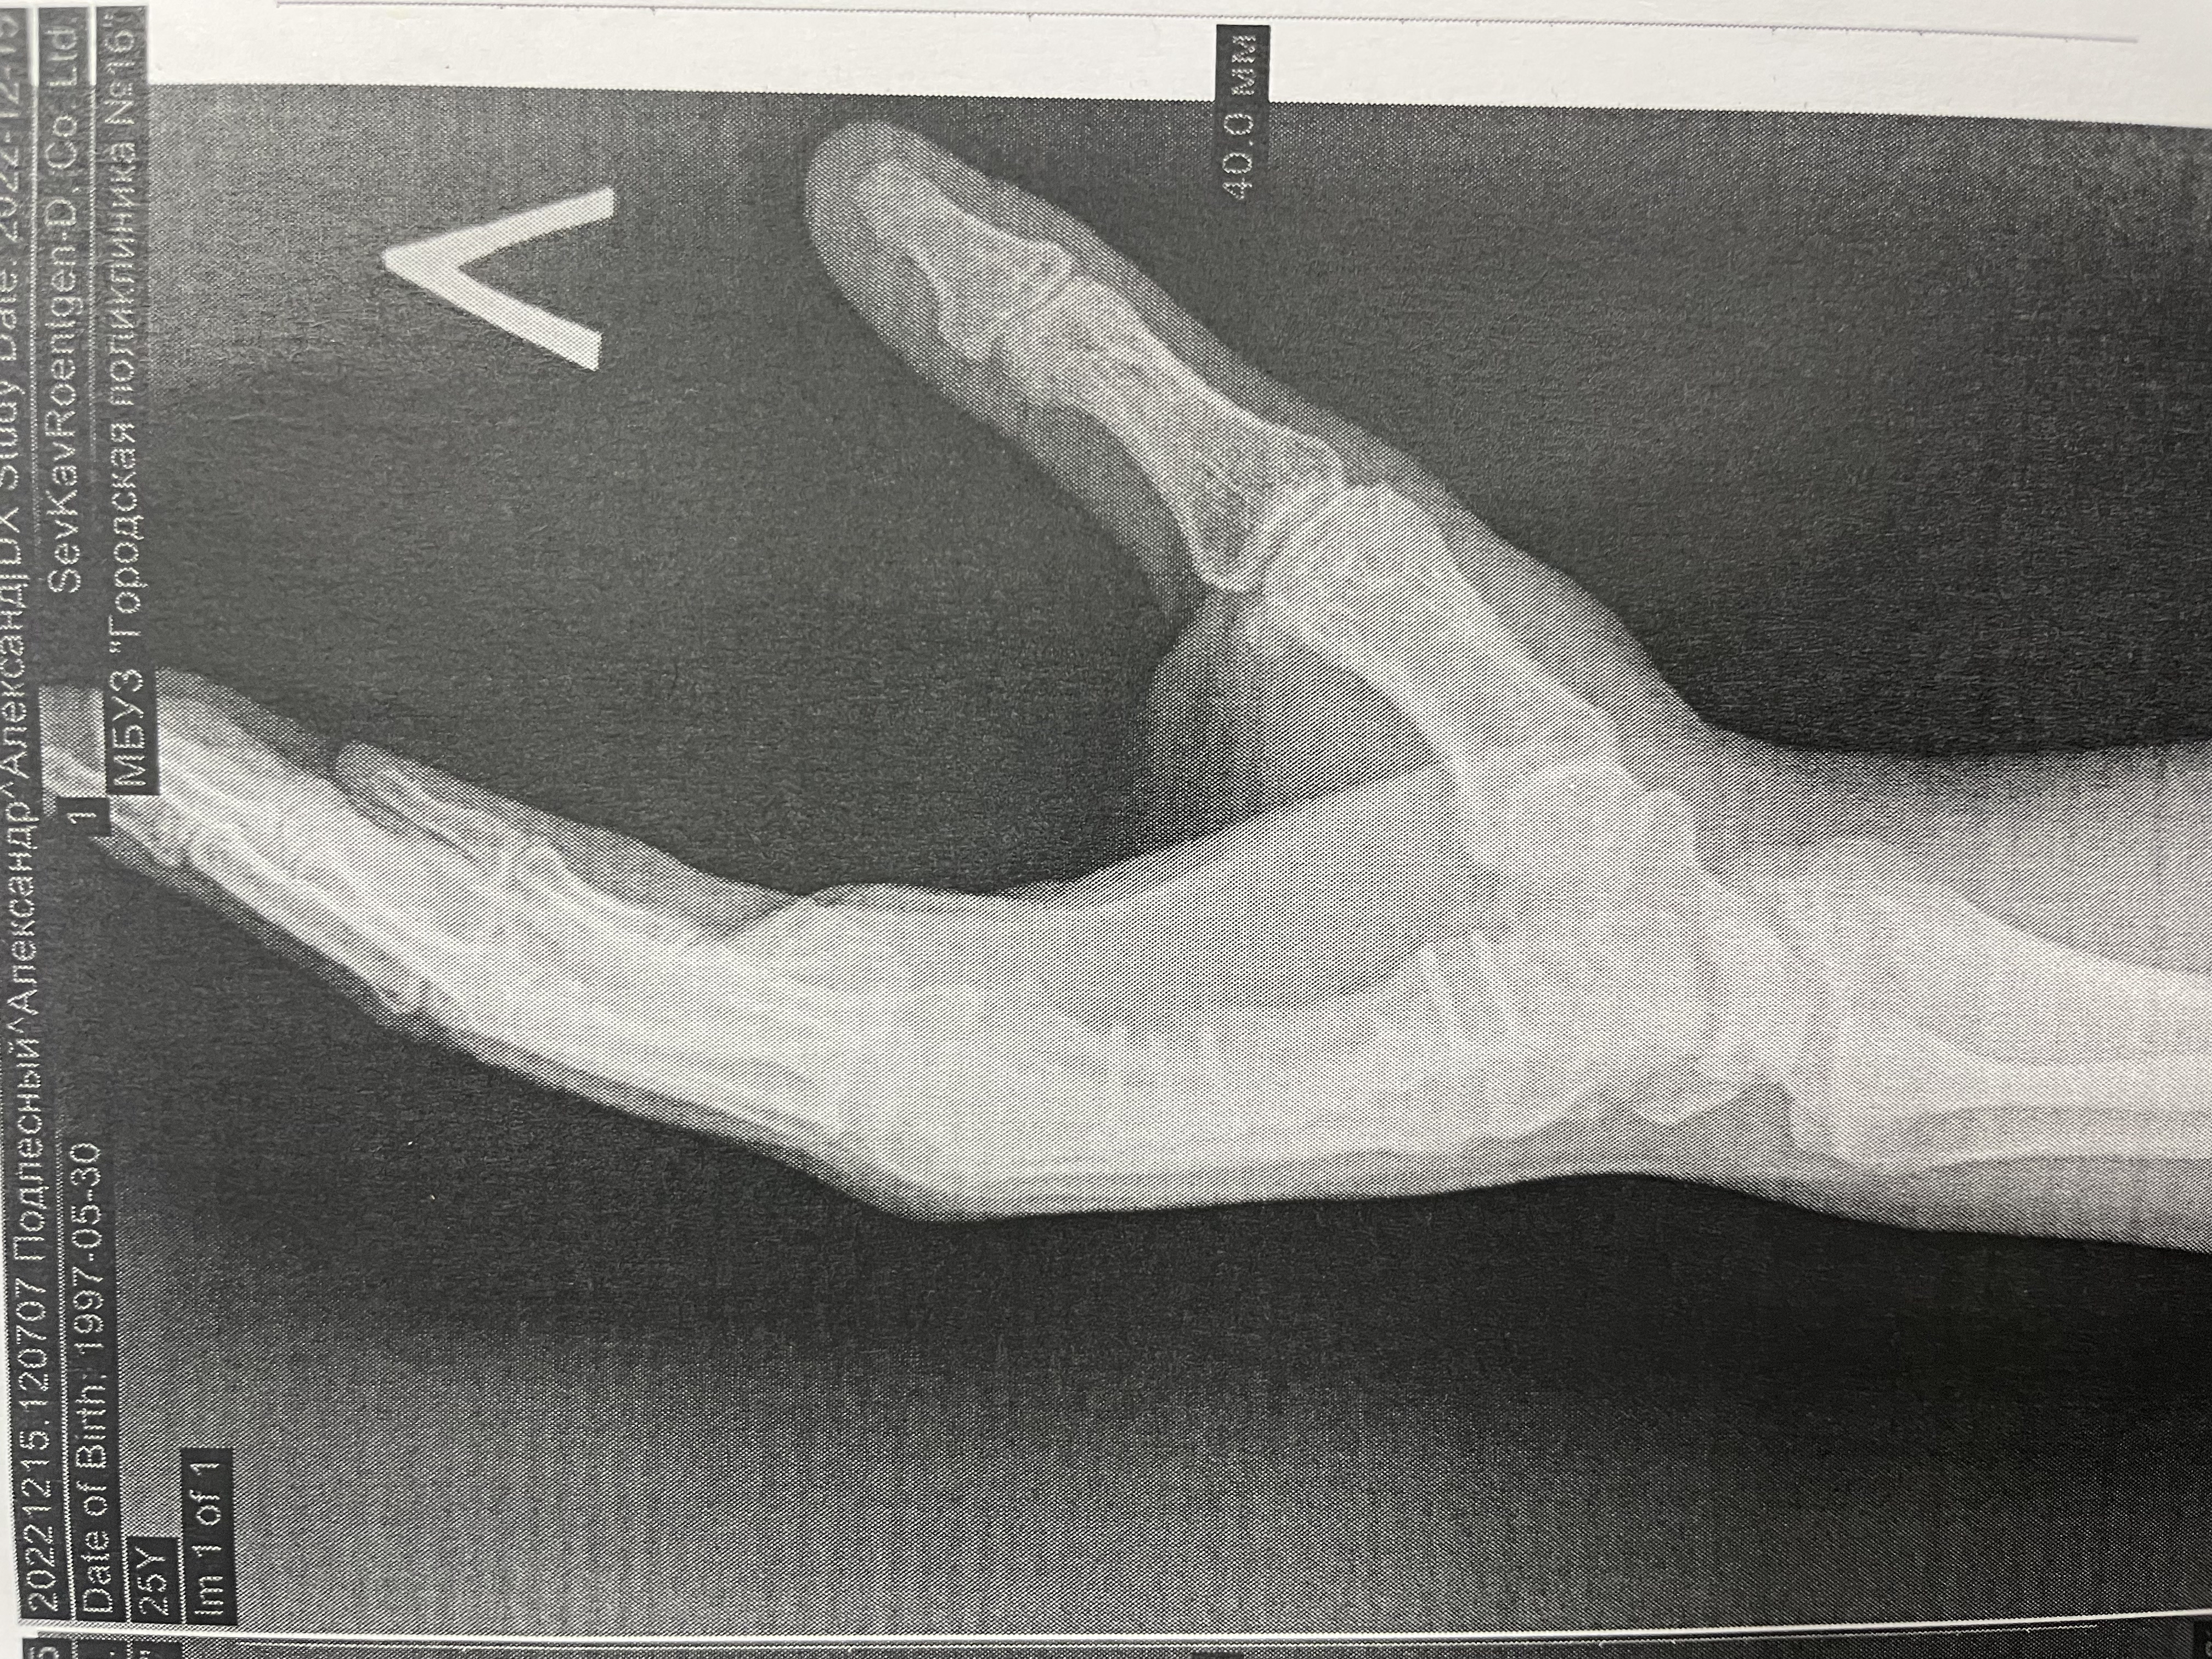

Переломы пястных костей диагностируются с клинического осмотра, во время которого врач оценивает симптомы и проводит физикальное обследование. Основным методом диагностики является рентгенография, которая позволяет визуализировать состояние костей и выявить наличие перелома. В некоторых случаях может потребоваться компьютерная томография (КТ) для более детального изучения повреждений, особенно если есть подозрение на сложные или нестандартные переломы.

Пациент с переломом 5 пястной кости по типу «боксёрского» удара. На фото и видео — деформация и ограничение функции до вмешательства.

Клинический случай: остеосинтез перелома 2 пястной кости — до операции

Пациент с нестабильным переломом 2 пястной кости. Документируем боль, отёк и ограничения движений перед оперативным лечением.